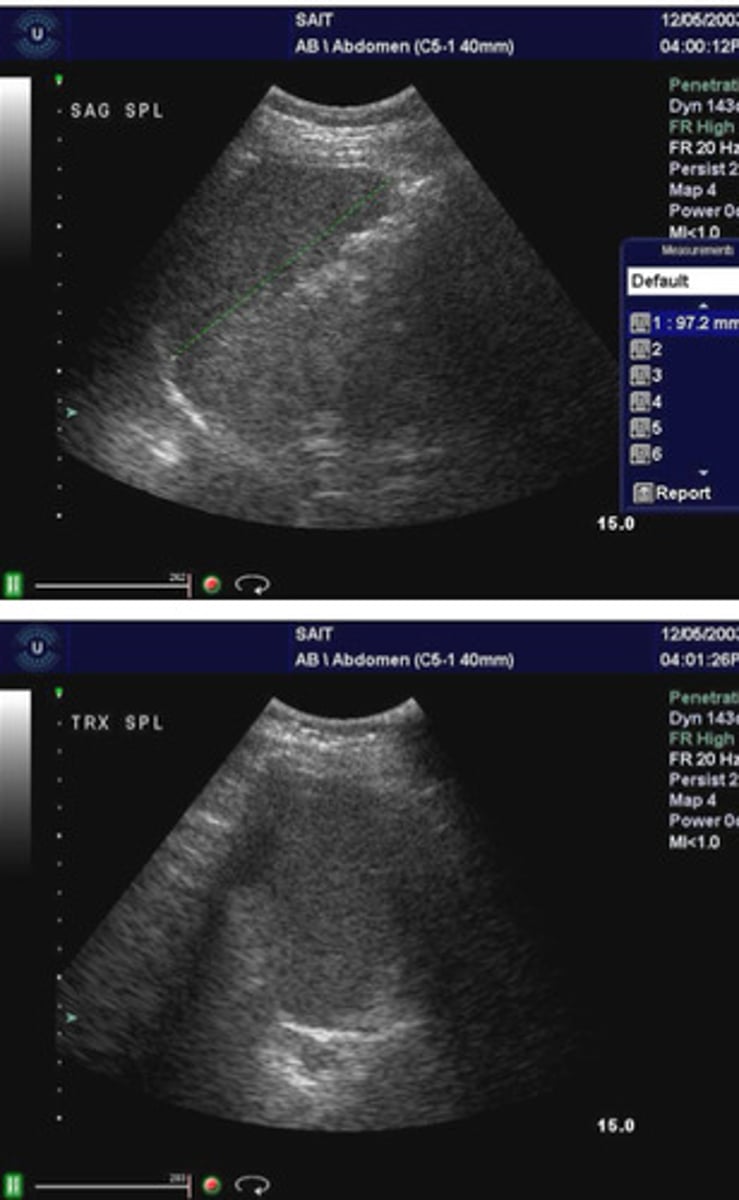

Hemangioma in the spleen

What does this image show

Larger and more complex usually than as seen in liver

Compare the sonographic appearance of a hemangioma in the spleen as compared to one in the liver